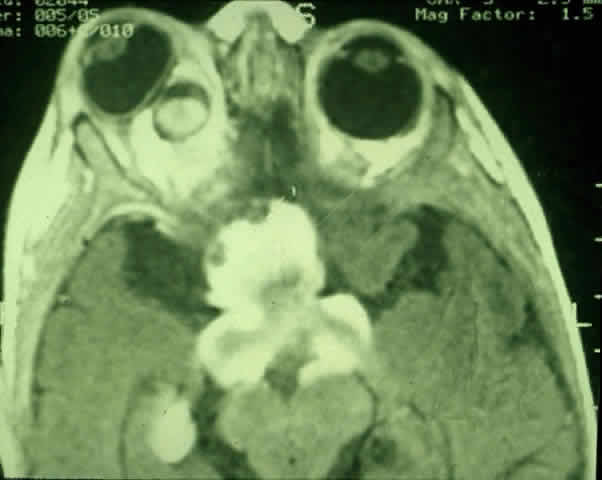

Fig. 2. Contrast-enhanced T1-weighted axial MRI of the orbits of the patient in Figure 1, demonstrating a large optic pathway glioma with posterior extension into the optic tracts and radiations. (Courtesy of Orlando Ortiz, MD, and Jeffrey Hogg, MD)

MRI has replaced CT scanning as the optimum test for imaging optic gliomas (Fig. 4 A and B). Optic gliomas have normal to slightly prolonged T1 relaxation times and appear isointense to slightly hypointense to normal brain on T1. Because many of these tumors have prolonged T2 relaxation times, images that are T2 weighted may be used to assess gross tumor margins and posterior extension.72 Optic nerve gliomas often demonstrate minimal enhancement after administration of contrast. To improve MR imaging of optic nerve lesions, a gadopentetate dimeglumine enhancement technique combined with fat suppression can be utilized. Unlike meningiomas, the thickened sheath from arachnoid hyperplasia associated with gliomas will not enhance.77 Although imaging should initially be performed in the axial plane to allow visualization of both the optic nerve and the posterior optic pathways, sagittal views are helpful in demonstrating chiasmal involvement; coronal views can be utilized to delineate intracanalicular tumor.78

Fig. 4. A. T1-weighted sagittal MRI of a patient with neurofibromatosis type 1, demonstrating enlarged optic chiasm consistent with optic glioma. B. T1-weighted coronal image with gadolinium and fat suppression in the same patient, demonstrating the chiasmal glioma.